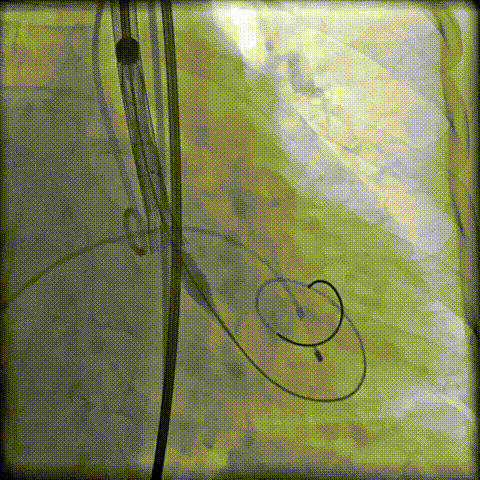

第一次定位释放

工作位瓣膜“上跳“,完全回收后二次定位